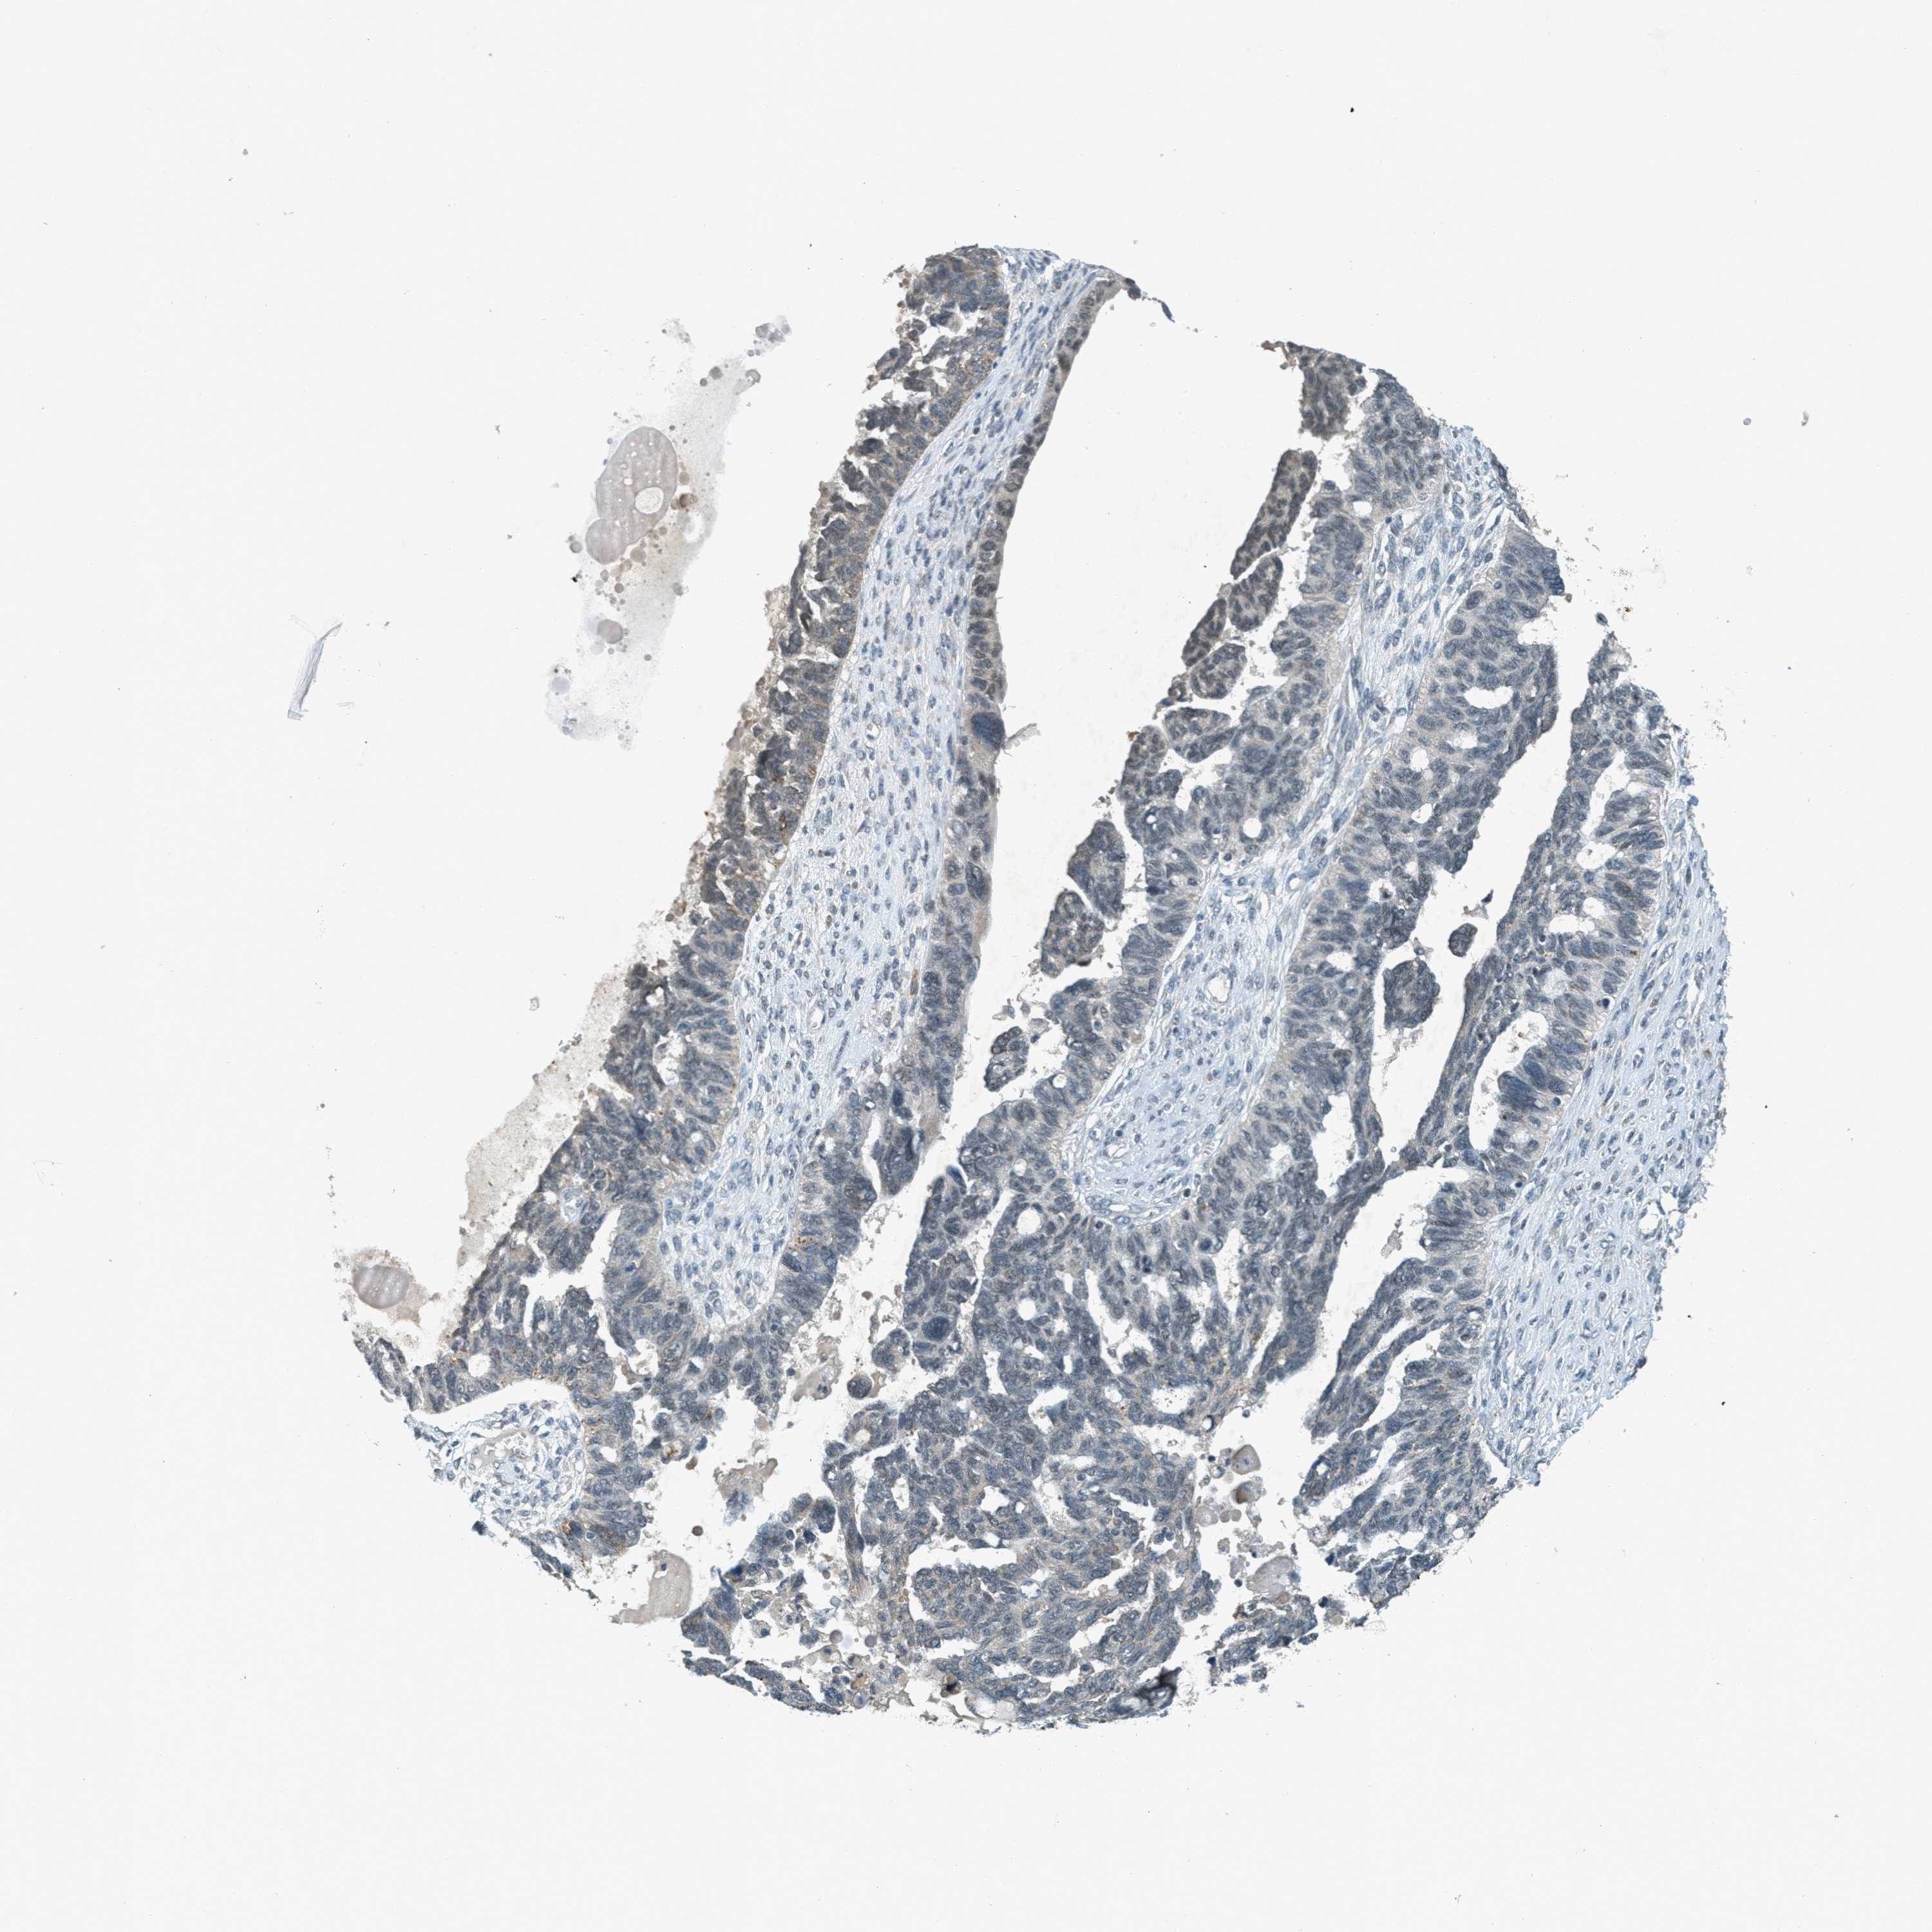

OVARIAN CANCER - Protein expressioni

A mouse-over function shows sample information and annotation data. Click on an image to view it in a full screen mode. Samples can be filtered based on level of antibody staining by selecting one or several of the following categories: high, medium, low and not detected. The assay and annotation is described here.

Note that samples used for immunohistochemistry by the Human Protein Atlas do not correspond to samples in the TCGA dataset.

Antibody stainingi

Antibody staining in the annotated cell types in the current human tissue is reported as not detected, low, medium, or high, based on conventional immunohistochemistry profiling in selected tissues. This score is based on the combination of the staining intensity and fraction of stained cells.

Each image is clickable and will lead to virtual microscopy that enables deeper exploration of all samples and also displays staining intensity scores, fraction scores and subcellular localization as well as patient and tissue information for each sample.

Antibody HPA036786

Antibody CAB017849

Cystadenocarcinoma, serous, NOS